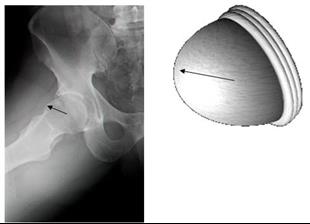

ד"ר דוד מורגנשטרן רופא ויועץ הסגל האולימפי, נבחרת ישראל בטאקוונדו, עמית (מומחה) ראשון בארץ ברפואת ספורט מטעם החברה לרפואת ספורט והמועצה המדעית בישראל. הקים ושימש כמנהל מרכז הספורט בבי"ח מאיר – כ"ס, ואורתופד של הסגל האולימפי. מומחה לניתוחי ארתרוסקופיה של מפרקי הירכיים.

למאמר בנושא ארתוסקופיה של מפרק הירך לחצו כאן

מומחה בכירורגיה אורתופדית, עמית ראשון בישראל ברפואת ספורט (המועצה המדעית).תואר שני במנהל מערכות בריאות (MHA) אוניברסיטת בן גוריון.השתלמות בטכניקות מתקדמות בארתרוסקופיות של מפרק הירך, ריאז, שוויץ (04'), קורס מתקדם Sports Hip Surgery באוניברסיטת וורוויק (Warwick Univ.) שבקובנטרי, אנגליה.השתלמות בארתרוסקופיות של מפרק הירך, ווייל, קולורדו, ארה"ב.